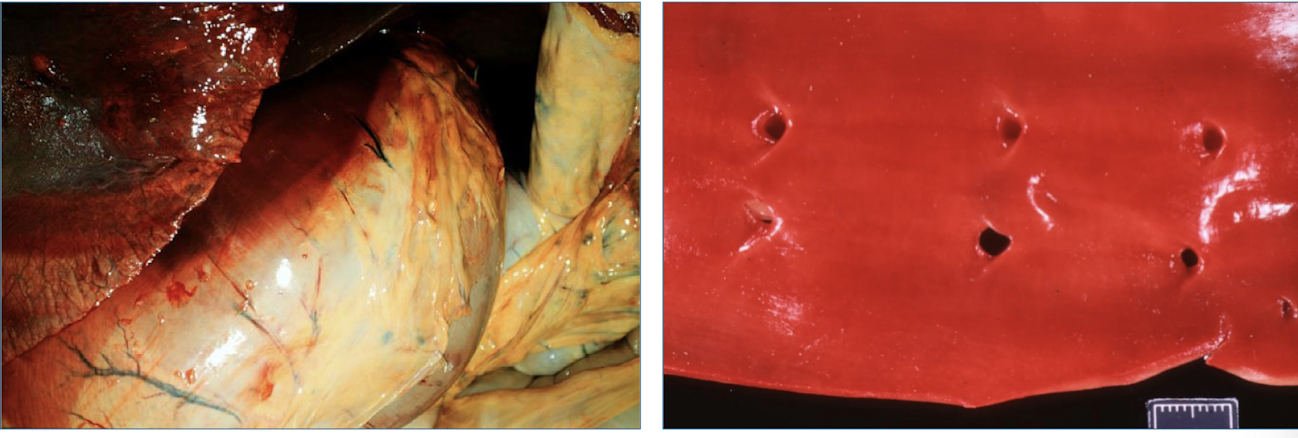

livor mortis/ hypostatic congestion

gravitational pooling of blood on the dependent (down) side of the carcass

What type of animals would you be able to physically see livor mortis?

skin of pale-skinned, sparsely haired animals (pigs)

When does livor mortis begin? What happens when you palpate the carcass?

0.5 - 2 hours after death

blanches on palpation

When does livor mortis become permanent?

once the blood clots → static or “fixed” after 8-12 hours

T/F: Pooled blood will remain on the original down side.

TRUE